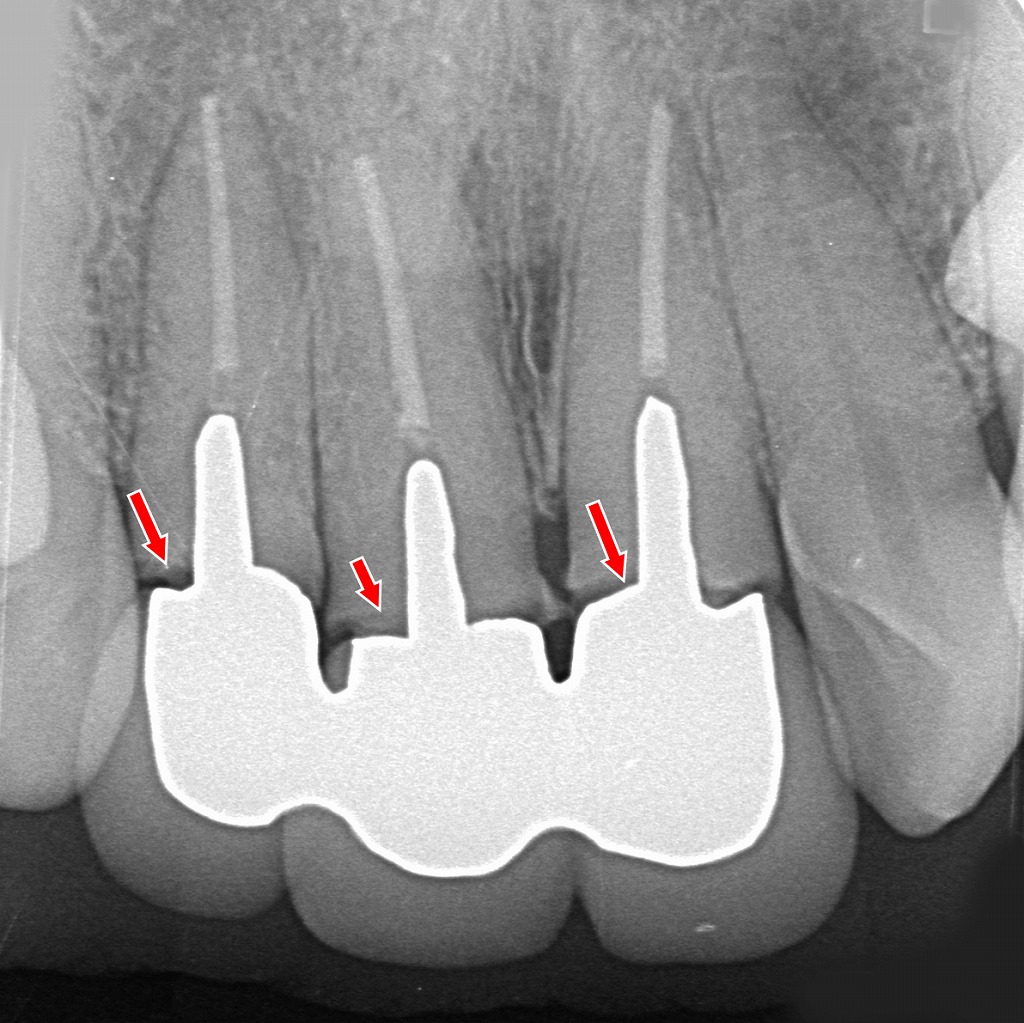

こちらのデンタルX線写真では、上顎前歯部の3本連結クラウン(ブリッジ状の補綴物)が、いずれも支台歯レベルで破折している所見が読み取れます。赤矢印の部位が破折ラインを示しています。

■ 画像の解説

上顎の前歯3本が連結されたクラウンの内部にある支台歯(ポストの入った根管治療歯)が、根元付近で折れてしまっている状態です。

赤い矢印で示した部分では、

- 支台歯とクラウンの境界が不自然に離開

- 根の内部にあるポストの周囲で透過像の乱れ

- 根の輪郭が一筋途切れるように写る

といった、典型的な歯根破折のX線像が確認できます。

破折が起きると、クラウンは一見ついているように見えても内部では支えが失われ、咬む力を支えられなくなります。

特に前歯部は力が集中しやすく、連結補綴+ポストコア+経年的な負荷が組み合わさると破折が起こりやすくなります。